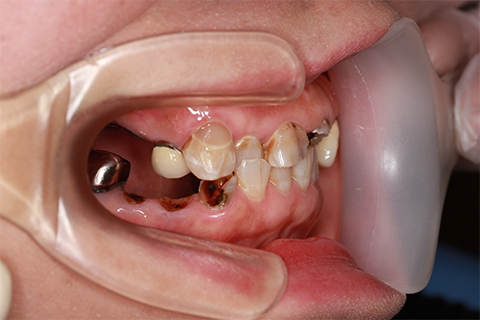

症例4

- 年齢・性別

- 60歳

- 治療期間

- 6ヶ月

- 抜歯

- 残根抜歯のみ

- 治療費

- 198万円

- 備考

- 右上5.6 右下5 左下4.5.6欠損

- 治療内容

- 6本のインプラントを右左側に2回に分けて埋入

- 施術の副作用(リスク)

- オペによる知覚障害。インプラントによる歯肉炎。インプラント脱落。